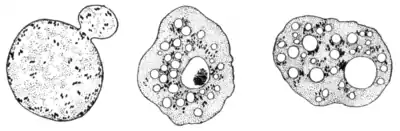

Moribund and fragmented parasites.—Moribund—it may be fragmented—free parasites (Fig. 18) are often a source of confusion to the beginner. Their nature is frequently misunderstood; they are sometimes erroneously termed "sterile bodies," an expression at one time frequently applied to the crescent-derived spheres (gametocytes). They are, in fact, mechanically-freed parasites expressed from blood corpuscles by the compression to which the blood is subjected between slip and cover-glass. The longer blood is on the slide—particularly if evaporation be not prevented by vaseline-ringing of the cover-glass—the more closely will the cover-glass approximate to the slip, the greater will be the pressure on, and consequent thinning and spreading out of, blood corpuscles and parasites, and the greater the liability to damage of these very delicate

Fig. 18.—Degenerating vacuolated plasmodia.

bodies. Frequently the artificially-freed parasites are broken into small fragments. The entire, as well as the fragmented parasites, on becoming free in the liquor sanguinis, tend to assume a spherical or disc-like form; at the same time the protoplasm of which they are composed seems to become diffluent, and the hæmozoin is resolved into a number of minute dust-like particles possessing active, brownian movement. Some of the spherical or disc-shaped bodies with dancing hæmozoin particles are really crescent-derived spheres or other forms of gametes. These are parasites which have escaped from corpuscles in a normal way, but which have become arrested in their evolution in consequence of the abnormal conditions in which they are placed in vitro; others are the remains of flagellated bodies, the microgamete filaments having broken away.